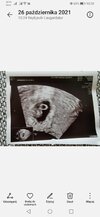

Cześć dziewczyny powracam z dobrymi wieściami 😊u nas na razie wszystko dobrze, serduszko bije. Według ostatniej miesiączki dziś 7+1 a według USG 6+5. A i zapomniałam napisać moja strasza siostra też jest w ciąży termin na 26 czerwca 😁

• Screenshot_20211026_102828_com.android.gallery3d.jpg

Screenshot_20211026_102828_com.android.gallery3d.jpg

218,5 KB · Wyświetleń: 89